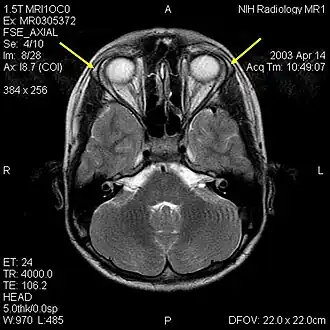

![]() MRI мозга 12-летнего подростка с тройным синдромом видны гипопластичные слезные железы (желтые стрелки) | |